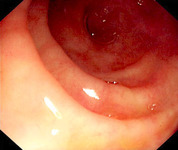

Laceração de Mallory-Weiss: a laceração com sangramento ativo aparece como um defeito longitudinal vermelho com mucosa circundante normal

Do acervo de Juan Carlos Munoz, MD, University of Florida